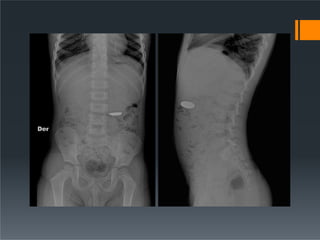

ď‚§ For identification and localization of foreign bodies.

ď‚§ POSITION of the patient:

I. Patient turned onto the side of examination with hands

resting near the head

II. Hips and knees flexed for stability

III. Median sagittal plane parallel to table

IV. Vertebral column positioned over midline of the table

V. Immobilization band applied across pelvis

VI. Cassette centered at the level of iliac crest

VII. Vertical central ray directed to the center of

the cassette.

ď‚§ Picture criteria: The prevertebral space along

with the abdominal aorta.

Lateral ď‚§ For identificationand localization of foreign bodies. ď‚§ POSITION of the patient: I. Patient turned onto the side of examination with hands resting near the head II. Hips and knees flexed for stability III. Median sagittal plane parallel to table IV. Vertebral column positioned over midline of the table V. Immobilization band applied across pelvis VI. Cassette centered at the level of iliac crest VII. Vertical central ray directed to the center of the cassette. ď‚§ Picture criteria: The prevertebral space along with the abdominal aorta.